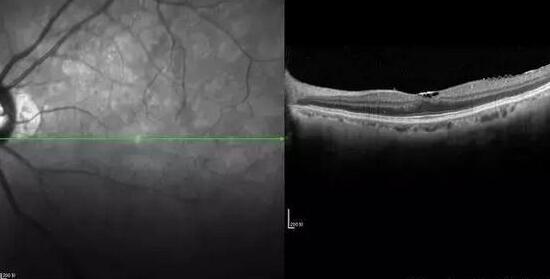

黄斑前膜